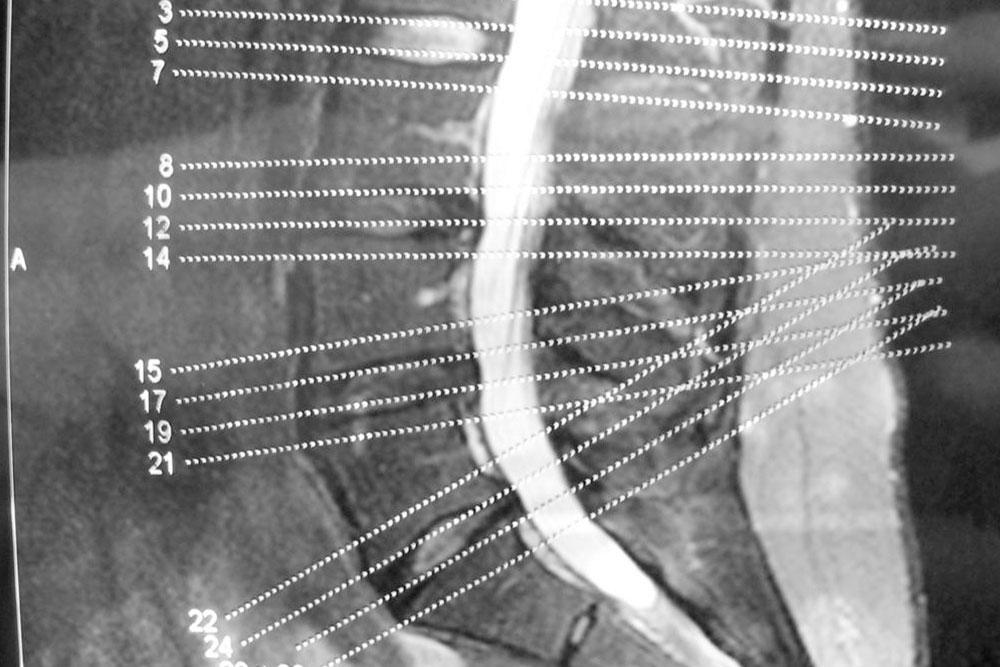

The spinal column consists of spinal discs that perform the task of providing padding between the vertebrae, i.e., the series of small bones that make up our backbone. They also act as shock absorbers and help the back remain flexible. As we age, these discs start gradually losing their elasticity property.

A common cause of this condition is the drying of your spinal discs. As you age, the water in the spinal discs dries out, flattening the spinal disc. A flattened spinal disc cannot absorb shock and they fail to provide padding to the vertebrae. Another cause of this disease can be a crack in the spinal disc. If the walls of the disc tear out, then there is a high chance that the soft core of the disc might push through the cracks and cause the disc to swell or, in the worst case, slip off.

This disease affects the facet joints, which are the joints that protect the vertebra in the spinal column from both sides. These joints make it possible for the spine to bend effortlessly.

The facet joints are lined with cartilages that cushion the joint and make sure that two adjacent vertebrae can glide smoothly against one another.